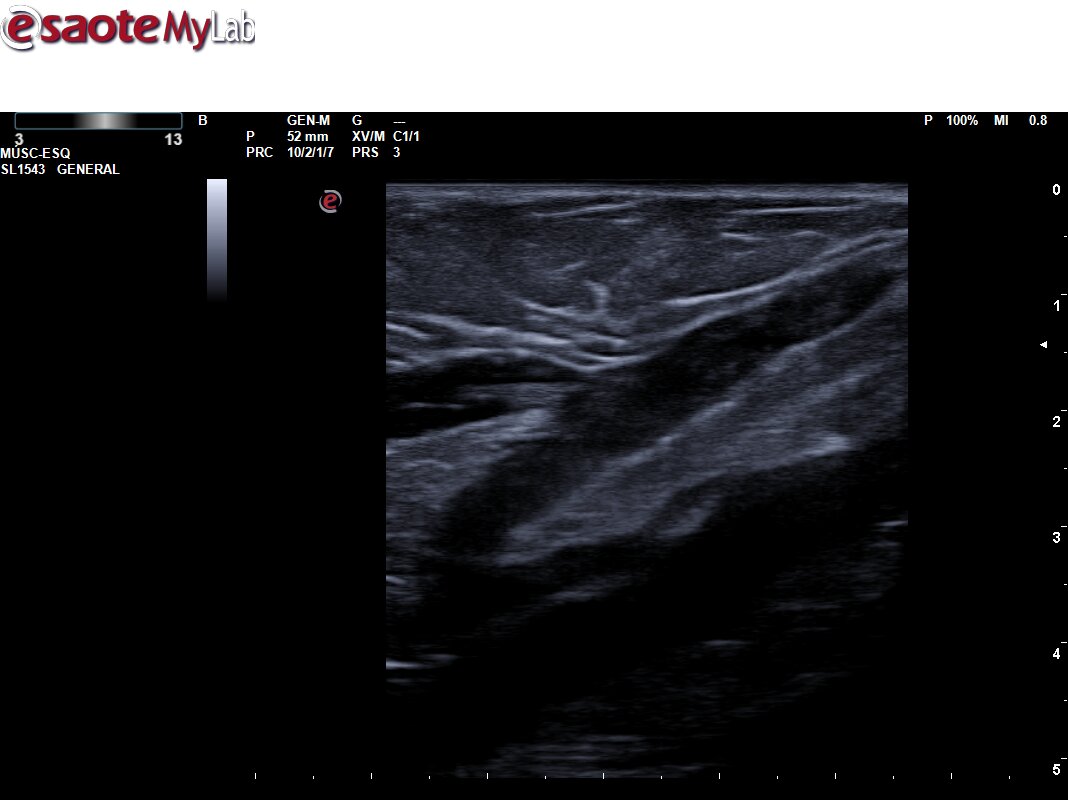

Hallazgos ecográficos

Ecografía primaria: Se explora sistema venoso profundo de MII presentando completa compresibilidad y Doppler + en la exploración extendida, así como ausencia de contenido ecogénico. Se amplía estudio a sistema superficial, apreciándose a nivel de Safena menor contenido hiperecogénico en una extensión superior a 5 cm, próximo a la desembocadura en vena poplítea. Ausencia de compresibilidad.

Ecografía urgencias: Se explora sistema venoso profundo de MII no apreciándose signos de trombosis. Sistema venoso profundo compresible, permeble a flujo fásico con movimientos respiratorios y maniobras de compresión. Vena safena menor izquierda no compresible, aumentada de calibre y con contenido ecogénico en todo su trayecto. Hallazgos compatibles con tromboflebitis superficial extensa.